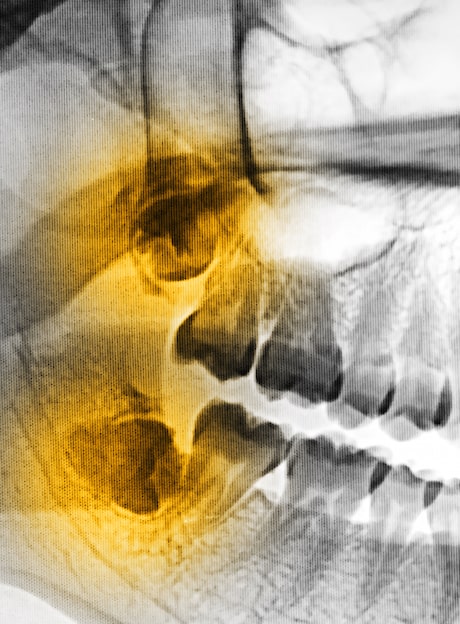

SECTIONING A TOOTH

Some teeth require sectioning. Sectioning is a very common procedure done when a tooth is firmly anchored in its socket or the root is curved and the socket can’t expand enough to remove it. The surgeon cuts the tooth into sections, then removes each section separately.